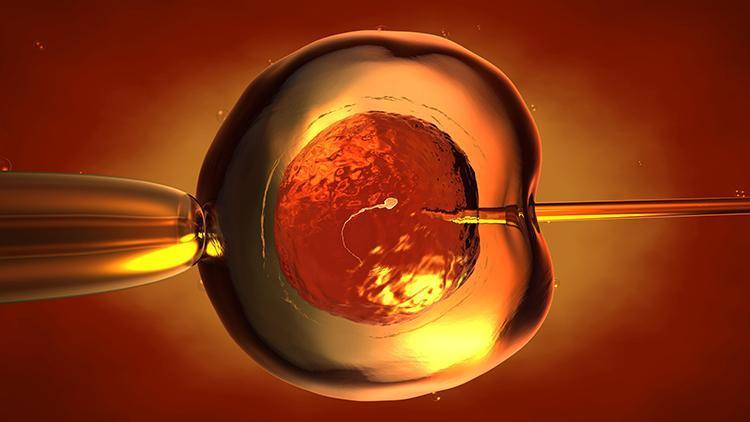

Erkekten alınan sperm ile kadından alınan yumurta yani oositin, laboratuvar ortamında döllenmesi ve gelişen embriyonun kadının rahmine yerleştirilmesine tüp bebek denir. Kadın Doğum ve Tüp Bebek Uzmanı ve Embriyolog Op. Dr. Öznur Dündar Akın, tüp bebek tedavisindeki merak edilenleri anlattı.

Dördüncü aşama: Özenle seçilen yumurta ve spermlerin; laboratuvarda “döllenme” aşaması ise dördüncü aşamada gerçekleşir.